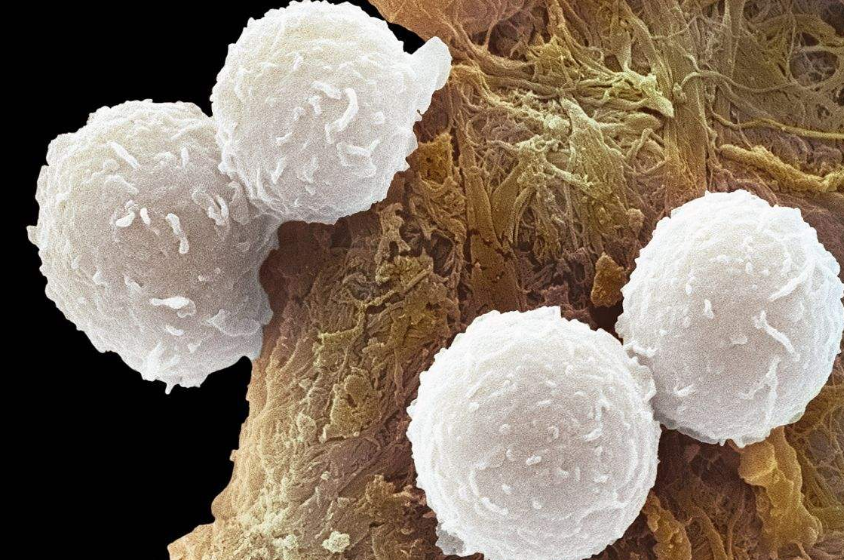

关于白血病靶向药——格列卫的介绍...

印度格列卫(伊马替尼)适应哪些疾病症状...